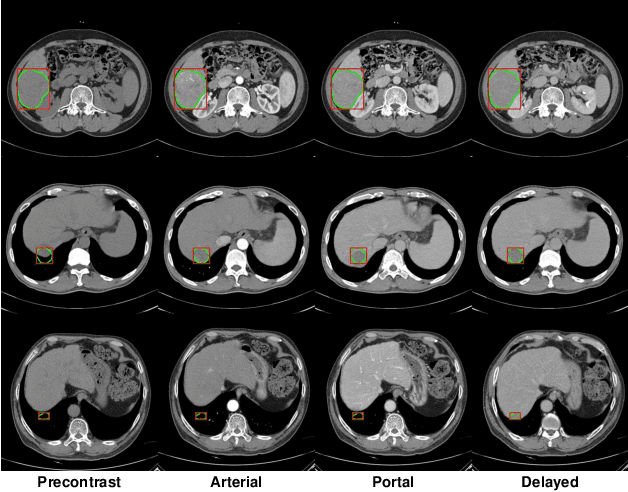

The computer-aided diagnosis of focal liver lesions (FLLs) can help improve workflow and enable correct diagnoses; FLL detection is the first step in such a computer-aided diagnosis. Despite the recent success of deep-learning-based approaches in detecting FLLs, current methods are not sufficiently robust for assessing misaligned multiphase data. By introducing an attention-guided multiphase alignment in feature space, this study presents a fully automated, end-to-end learning framework for detecting FLLs from multiphase computed tomography (CT) images. Our method is robust to misaligned multiphase images owing to its complete learning-based approach, which reduces the sensitivity of the model's performance to the quality of registration and enables a standalone deployment of the model in clinical practice. Evaluation on a large-scale dataset with 280 patients confirmed that our method outperformed previous state-of-the-art methods and significantly reduced the performance degradation for detecting FLLs using misaligned multiphase CT images. The robustness of the proposed method can enhance the clinical adoption of the deep-learning-based computer-aided detection system.